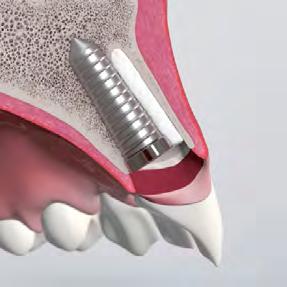

• Achieve primary stability and maintain a buccal gap >2 mm

Buccal gap bone grafting (with low substitution material)

While implant positioning is critical, it does not prevent post-extraction remodeling. Biomaterials play a key role in managing the peri-implant gap and maintaining long-term hard- and soft-tissue stability.

“Placing an implant does not stop facial bone remodeling. The implant is a passive occupant — reconstruction with biomaterials is required to maintain volume and long-term hard- and soft-tissue stability.”